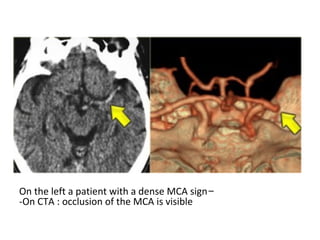

c) Hyperdense artery :

-Represents acute thrombus within the vessel

-Most commonly recognized with basilar and

proximal MCA thrombosis

-False positives can occur if a vessel is partially

calcified or if the haematocrit is raised (i.e.

polycythaemia)

-On the left a patient with a dense MCA sign

-On CTA : occlusion of the MCA is visible

Gradient Echo shows blooming artifact (red arrow) in the right proximal MCA

which represents intraluminal thrombus and in the MRI correlate to the

hyperdense artery sign that can be seen on CT